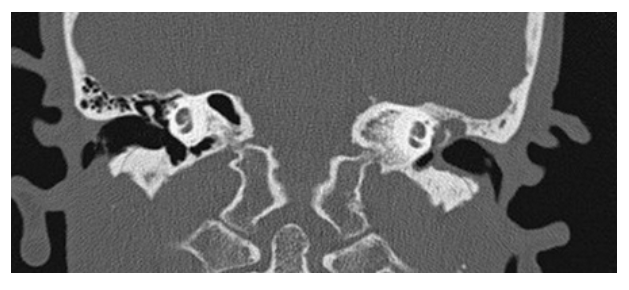

What does the figure show?

Cholesteatoma. Coronal NECT shows soft tissue density in the left middle ear with thickening of the tympanic membrane. The left scutum has a blunted appearance (compared to sharp tip of normal right side). Findings are consistent with a cholesteatoma.

What is A

Cholesteatoma. Axial NECT of the temporal bones shows soft tissue in the left middle ear located lateral to the ossicles in the epitympanum (Prussak space). Mastoidectomy has previously been performed on the right. Coronal CT

What is B

Cholesteatoma. Axial NECT in same patient shows soft tissue in left middle ear within Prussak space of the epitympanum with blunting of the scutum. Right mastoidectomy is present.